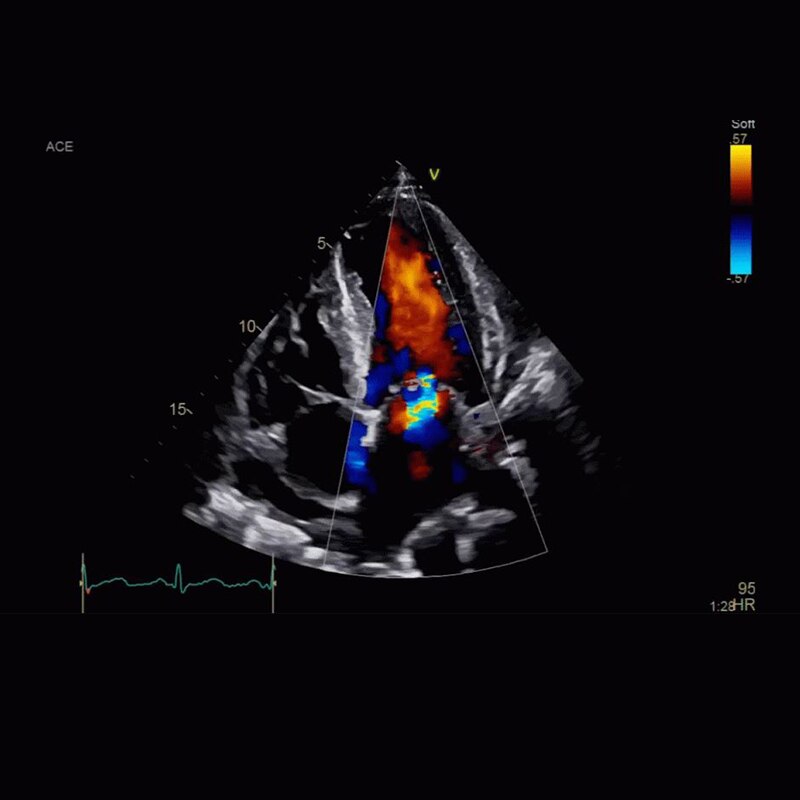

Vivid™ Portfolio

Cardiac Auto Doppler automatically provides Doppler measurement results for the most common parameters, with minimal user guidance.

Vivid™ E95

cSound beamforming technology for exceptional visualization quality with impressive resolution in 2D, color flow, Doppler and 4D formats.

Semi-automated 3D valve assessment.

Cardiology Solutions Aortic Stenosis vivid e95 clinical 2d